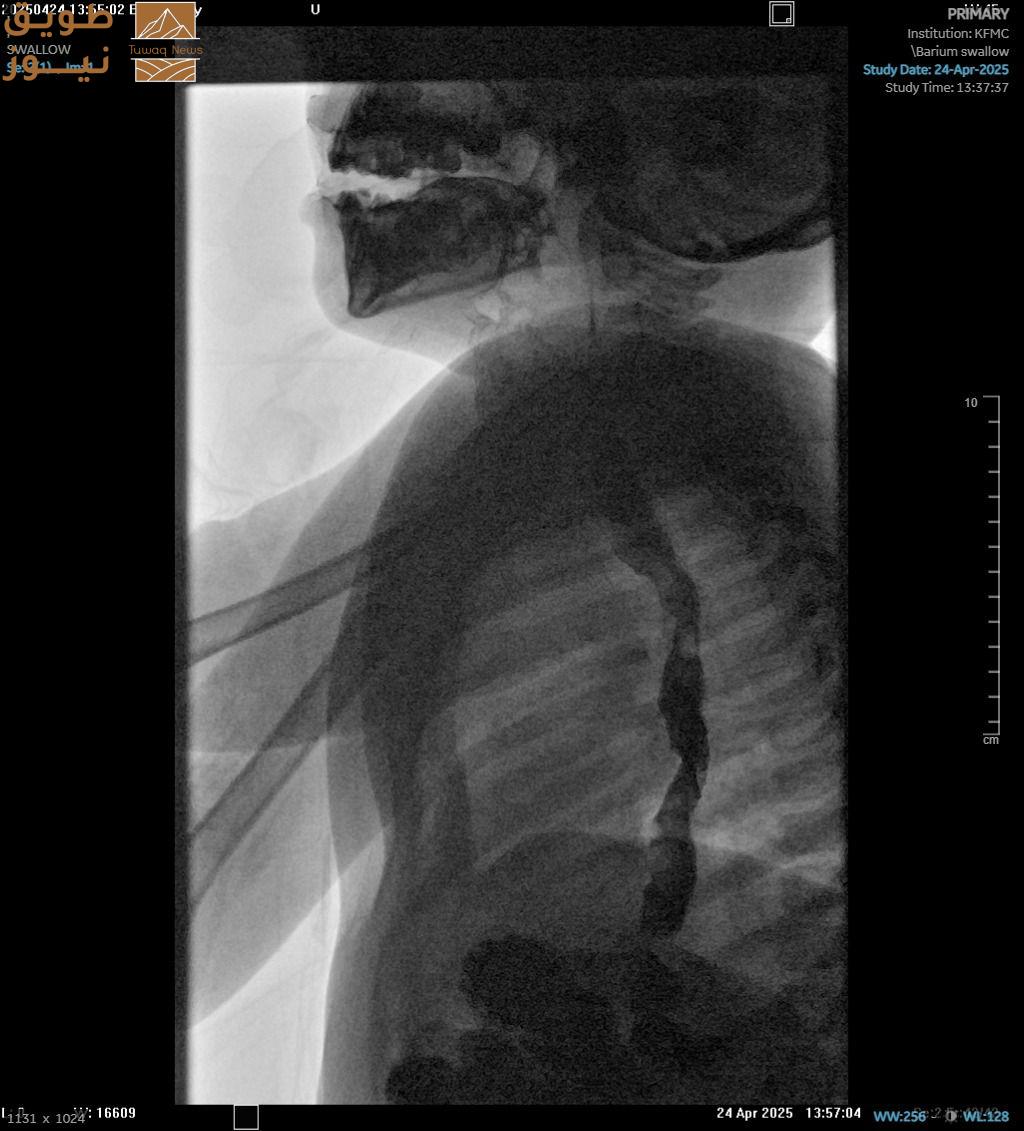

مدينة الملك فهد الطبية: منظار غير جراحي يُعيد الحياة لطفلة الـ 4 سنوات

نجح فريق طبي في مدينة الملك فهد الطبية إحدى مكونات تجمع الرياض الصحي الثاني ، في إجراء منظار علاجي متقدم غير جراحي (POEM) لطفلة تبلغ من العمر 4 سنوات، في حالة وصفت الأولى على مستوى المملكة ، كانت تعاني من تعذر الارتخاء المريئي، ( الاكاليزيا)

وفشل النمو لأكثر من عامين، مما سبب فقداناً لوزنها بقرابة 20 كيلو غرام.

وبينت المدينة أن الطفلة خضعت سابقًا لعدة جلسات توسيع للمريء دون تحسن، إلى أن تمكن الفريق الطبي من إجراء المنظار عبر الفم خلال 15 دقيقة فقط وبلا أي مضاعفات، لتغادر المريضة المدينة الطبية في اليوم الثالث.

وقالت : ” يُعد هذا التدخل الطبي الأول من نوعه على مستوى المملكة في شريحة الأطفال وخصوصًا في هذا العمر الصغير، حيث تُعتبر التدخلات الجراحية في مثل هذه الحالات عالية الخطورة، إذا تصاحبت مع نزول للوزن حيث كان وزن الطفلة 12 كجم فقط، وتمكّنت الطفلة من استعادة قدرتها على البلع الطبيعي في اليوم الثالث بعد المنظار، كما استعادت وزنها بعد أن خسرت نحو 20 كيلوغرامًا.

الجدير ذكره ، أن هذا الإنجاز يؤكد كفاءة الكوادر الطبية الوطنية ومواكبتها لأحدث الممارسات العالمية، بل وتحقيق نتائج استثنائية من حيث سرعة الأداء وسلامة المريض، إذ أن المعدل العالمي لإجراء مثل هذه العمليات بالمناظير يتراوح 45 إلى 90 دقيقة .